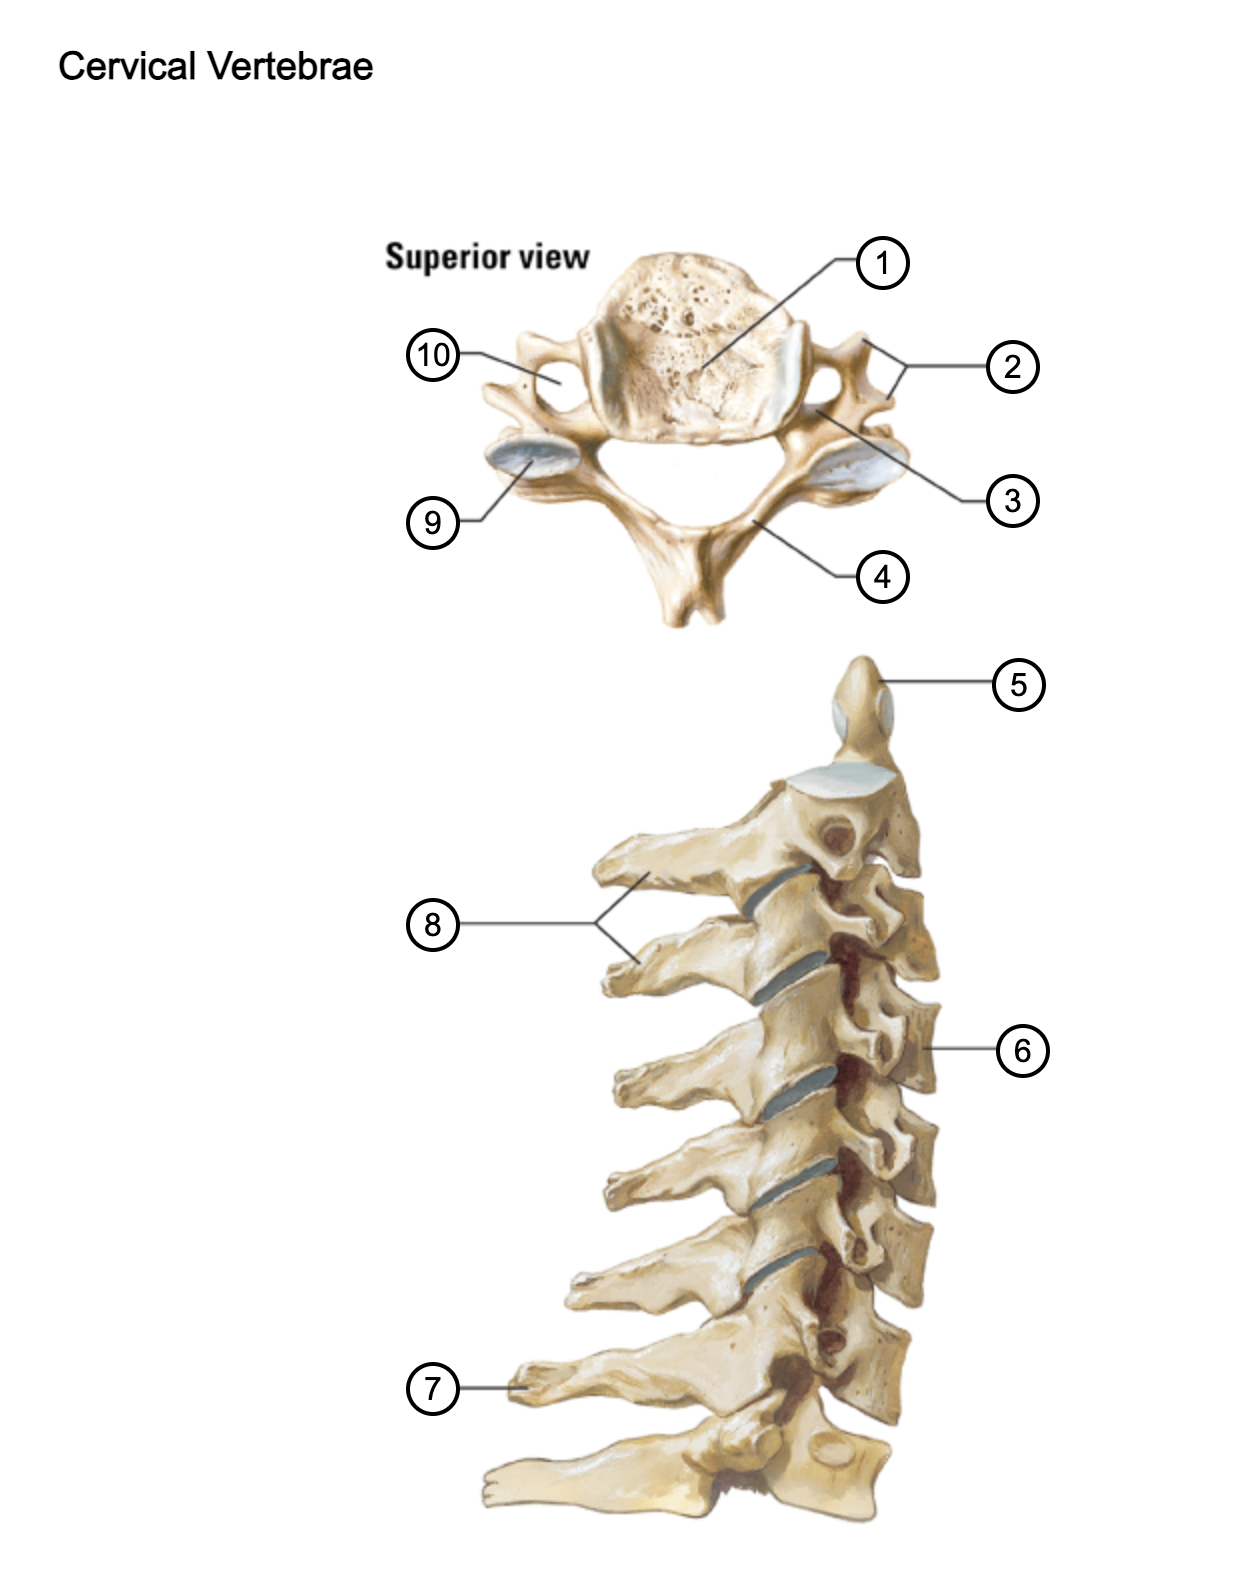

1

vertebral body

2

transverse process

3

pedicle

4

lamina

5

dens axis

6

vertebral body of C4

7

spinous process C7 (vertebra prominens)

8

spinous processes (C2 and C3)

9

superior articular process of C4

10

transverse foramen